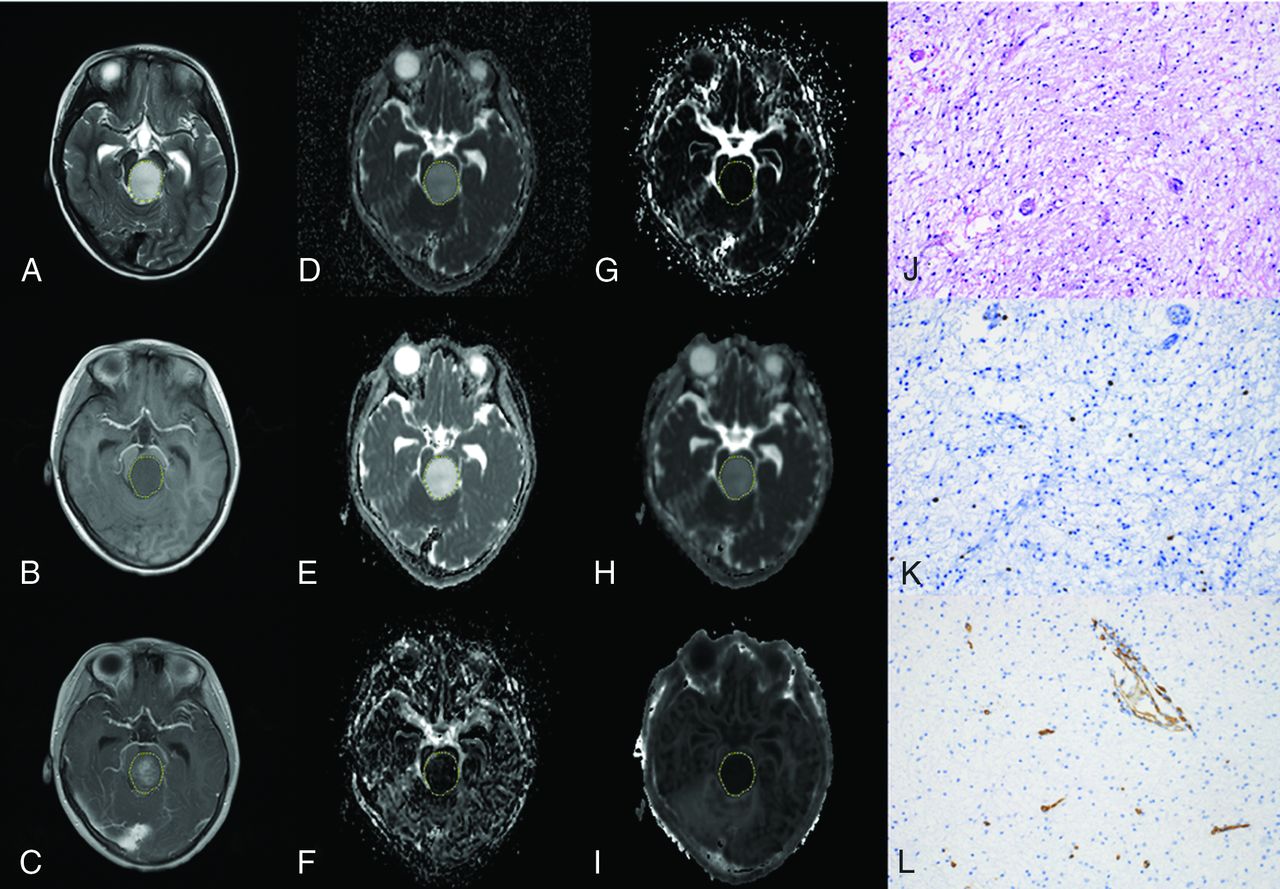

The quantitative MR imaging parameters of each pediatric brain tumor type are shown in the Online Supplemental Data. As shown in Table 2, inter- and intrareader agreement was good for the measurements of conventional DWI, IVIM, and DKI parameters (intraclass correlation coefficient = 0.771–0.984). The comparative results of histologic and quantitative MR imaging parameters between low- and high-grade PITs are shown in Table 3. For the diffusion parameters, the ADCROI, ADCVOI, DROI, DVOI, DkROI, and DkVOI values were significantly lower in high-grade tumors than in low-grade tumors (all, P < .001), whereas the KROI and KVOI values of high-grade brain tumors were significantly higher than those in low-grade tumors (P < .001) (Figs 1 and 2). The high-grade brain tumors tended to have higher f values, but the difference was not significant (P > .05). For the histologic parameters, the cellularity and Ki-67 were significantly higher in the high-grade group than in the low-grade group (all, P < .05) (Figs 1 and 2).

A 15-year-old boy with medulloblastoma in the cerebellum (WHO grade IV). The lesion shows hyperintensity on the T2-weighted image (A), hypointensity on the T1-weighted image (B), and enhancement on the postcontrast T1-weighted image (C). The lesion (VOI) demonstrates hypointensity on the ADC map (D), D map (E), and Dk map (H) and hyperintensity on the D* map (F), f map (G), and K map (I), with values of 0.647 × 10−3mm2/s, 0.594 × 10−3 mm2/s, 0.778 × 10−3 mm2/s, 87.228 × 10−3 mm2/s, 6.312%, and 1.210, respectively. The pathologic diagnosis was medulloblastoma with a cellularity of 4927 cell/mm2 (J), a Ki-67 index of 80% (K), and an MVD of 1.4% (L) (original magnification × 200).